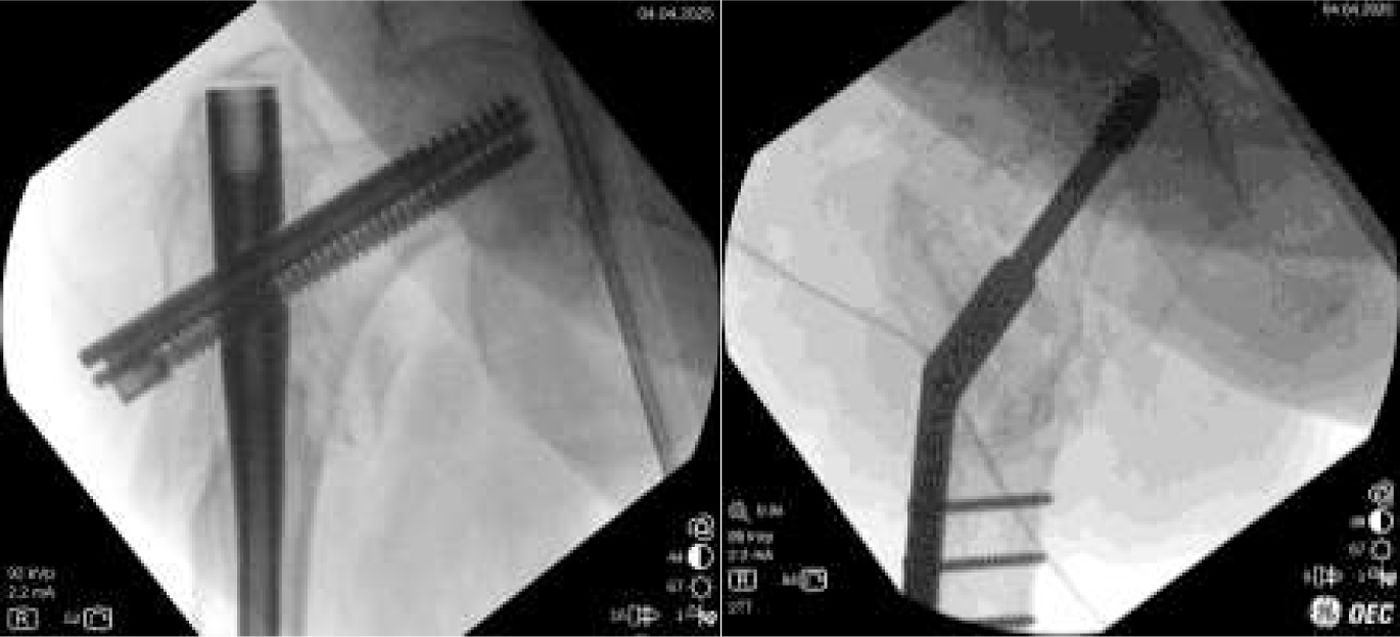

Final fixation and wound closingAfter plate gathering to the femoral shaft, get compression at nonunion site. It is quite important to avoid any distraction applied to the leg. Assure that no traction is given and compress slightly the limb. This is a very important point to assure proper compression and a buttress effect on the medial side of the nonunion. At this point, it maybe necessary to loosen a little bit the lowman retractor to facilitate compression.

Rotation of the limb is now assessed and corrected if necessary. With a lateral view of the proximal femur, the knee (intercondylar axis) should be aligned to get a 15° anteversion of the proximal femur.

Then, 3.5 cortical screws are applied. It is recommended that at least 6 bicortical screws with good purchase be inserted. If a longer plate is applied, the more distal screw can be a monocortical screw to diminish stress at the distal tip of the plate. If any screw is found not to hold properly, it may be useful to apply a wire cerclage over the plate.

Good purchasing is verified by moving the construct under fluoroscopic vision (Fig. 7).